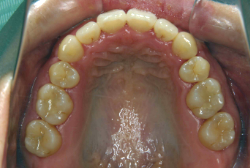

叢生(そうせい)

凸凹な歯並びのことを叢生といいます。矯正歯科に来院する患者様の主訴の中で、最も多いのが「配列の凸凹を真っ直ぐにしたい」というものです。歯の大きさと顎の大きさの調和がとれていないことが原因です。

凸凹を主体としたケースの場合、当院の平均治療期間は18ヶ月ですので、このケースは少し長めに経過しました。理由の一つは凸凹の程度がかなり重症だったと言うことですが、もう一つは、右下第2大臼歯が45度くらい前傾していたため、それを整直化させるために時間を要したと考えています。いずれにしても最終結果は大変よい状態と思います。

治療前は並びが乱れて見た目が悪いというのはもちろん問題ですが、歯科医学的に一番困るのは噛み合わせが悪いという点です。上下の犬歯(3番目の歯)は、上下的に離れた位置にあるため接触することができません。つまり歯としては存在していても、歯としては機能していないということです。